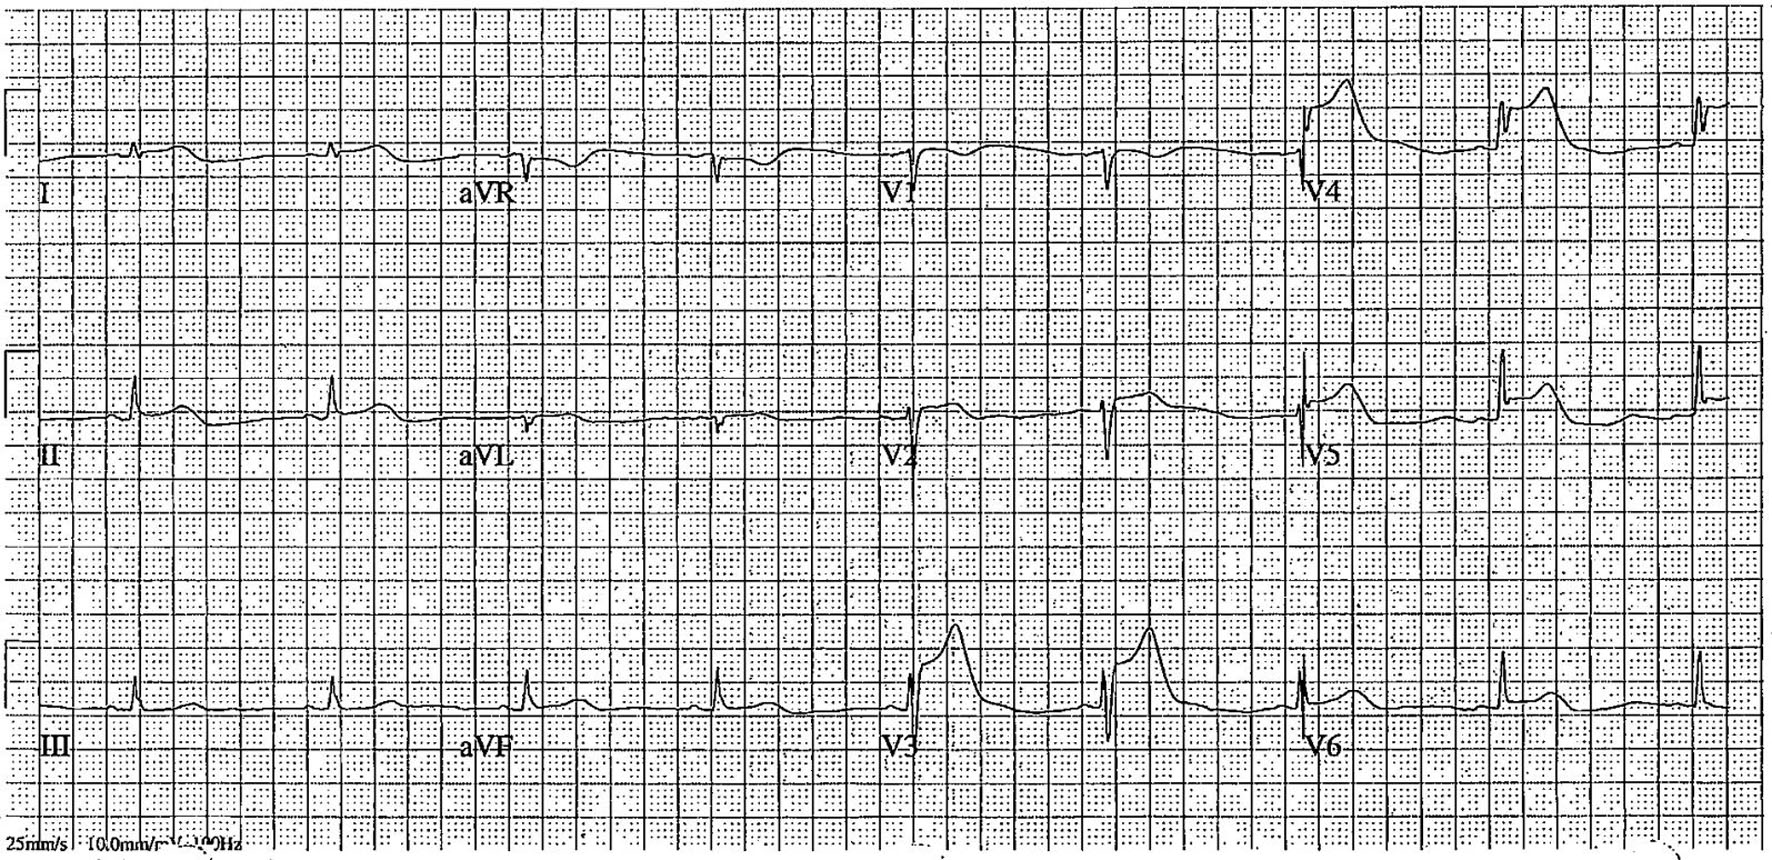

A 51-year-old woman with type 2 diabetes mellitus and a family history of coronary artery disease (CAD) presented for elective left heart catheterization (LHC). Outpatient coronary computed tomography angiography (CCTA) revealed severe proximal left anterior descending (LAD) stenosis, moderate multifocal right coronary artery (RCA) stenosis, and a coronary calcium score of 613. LHC confirmed 80% stenosis in the proximal LAD and proximal-to-mid RCA. Drug-eluting stents (SYNERGY 2.5 × 48 mm for LAD, 3.0 × 48 mm for RCA) were implanted following loading doses of aspirin (324 mg) and ticagrelor (180 mg) (Supplementary Videos 1 and 2, jmc.elmerpub.com). Within 2 h post-PCI, the patient developed syncope, hypotension, and ST-elevation in the inferior leads (Fig. 1). Differential diagnoses included acute in-stent thrombosis, stent malapposition, coronary artery dissection, or distal embolization. The patient was started on norepinephrine drip and returned to the catheterization lab.

Figure 1. Electrocardiogram post-syncope showing ST-elevation in leads V3–V6, suggestive of acute in-stent thrombosis in the left anterior descending artery.